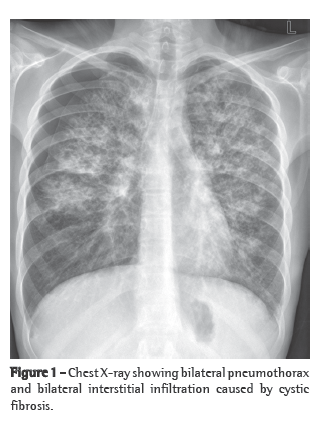

A male patient, aged 26 years, a native and resident of Sergipe, Brazil, was evaluated in the Thoracic Surgery Department of the Clementino Fraga Filho University Hospital of the Federal University of Rio de Janeiro due to a large pulmonary mass, detected through chest X-ray (Figure 1). The computed tomography scan of the chest provided little additional data. The patient presented cough with hemoptysis and dyspnea for two months prior to hospitalization. In his hometown, the case was investigated through fine-needle puncture of the lesion. The findings were consistent with a diagnosis of lymphoma. The patient was submitted to polychemotherapy and, since he did not improve, he decided to suspend treatment and come to Rio de Janeiro. Following negative extrathoracic staging for metastases, the patient was submitted to a mass biopsy, through minimal right thoracotomy. The histological findings confirmed the diagnosis of hemangiopericytoma. The preoperative pulmonary evaluation showed that the patient presented functional pneumonectomy, with a vital capacity of 54%, a forced vital capacity of 46% and a forced expiratory volume in one second of 41%. We therefore decided to perform a thoracotomy in order to resect the mass, due to the fact that the patient was young and in good general health, there were no signs or symptoms of distant metastases and there was no other efficient treatment for the patient.